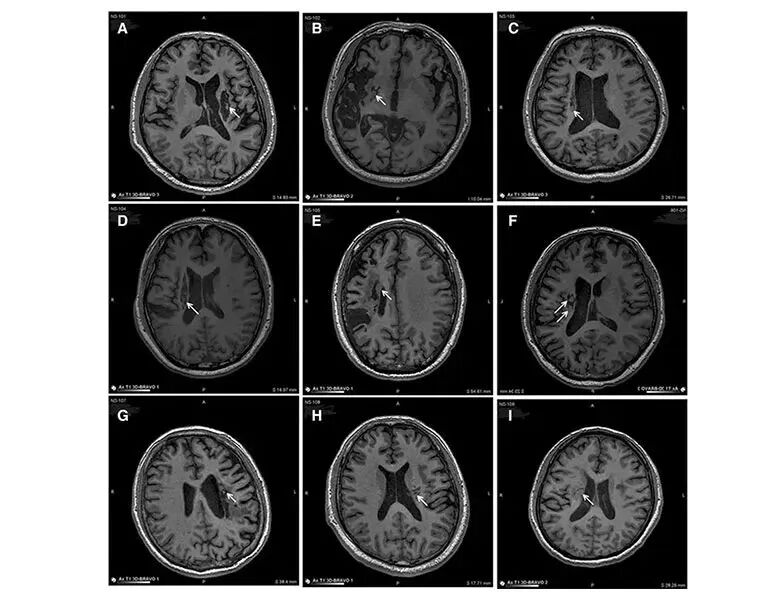

迄今为止,已有超200项应用各种干细胞方法治疗神经系统疾病的临床研究被注册,主要为多发性硬化症、中风、帕金森和脊髓损伤。以下是近年来干细胞在常见的几种神经系统疾病中的临床疗效。脑卒中可导致神经元损伤,在《STEM CELL TRANSL MED》上的一项研究显示,干细胞可再生修复受损的大脑神经元,从而恢复脑中风患者后遗症症状:在9名年龄不等的脑中风偏瘫患者实验中,应用干细胞移植到脑内梗塞灶取得了一定的临床效益。 △ 9例患者的影像学显示病变区域的组织都发生了明显变化从影像学上可以明显的看到,回输到脑内梗塞病灶的干细胞,通过分化为神经系统的各类细胞、分泌营养因子,促进神经和血管再生,修复受损的血-脑脊液屏障,减轻炎性反应等促进脑梗死动物的神经功能恢复,让9例临床患者偏瘫的症状得到了明显改善。在重塑血管,维持脑中风血流量上,干细胞利用旁分泌功能发挥了“强项”,分泌血管内皮生长因子(VEGF),促进脑血管新生,重塑血管,恢复内皮完整性减轻通透性,减少细胞凋亡。 △ 研究证实干细胞能重塑血管,维持中风后脑血流量当然,干细胞也将为阿尔兹海默症、帕金森病等神经退行性疾病患者带来新的治疗选择。《Advanced Science》上的文章表示:脐带间充质干细胞(hUC-MSCs)具有修复损伤神经细胞的功能,能够通过HGF-cMet-AKT-GSK3β通路调节tau蛋白磷酸化,显著提高阿尔茨海默病模型动物的学习记忆和认知能力。 △ HGF介导临床级人脐带间充质干细胞改善功能恢复在衰老加速的阿尔茨海默氏病小鼠模型中众多临床试验也表明,干细胞治疗阿尔兹海默病不仅能够调节脑内炎症性环境,而且促进神经再生和突触链接,有效改善病症,且安全无副作用。帕金森病(PD)是一种进行性的神经系统退行性疾病,多见于60岁以上群体,该疾病的特征在于大脑许多区域中特定脑细胞(神经元)的死亡,而干细胞疗法治疗帕金森疾病迎来新的突破。为改良细胞回输后存活率较低的问题,哈佛医学院将调节T细胞与iPSC衍生的中脑多巴胺神经元(mDANs)共同注射给动物模型,结果显示mDANs存活显著提高,且动物行为恢复迅速强健,为帕金森疾病治疗提供了一种新的可能选择。 △ 细胞联合细胞治疗帕金森病此外,一款针对帕金森症的干细胞疗法也取得了令人鼓舞的成绩。2023年8月,拜耳宣布了针对帕金森症的干细胞药物已经达到一期实验终点,并为患者带来了令人惊喜的结果,12位受试者被分为高剂量组与低剂量组,而后在接受细胞疗法一年内,他们均未出现不良事件。 △ 据帕金森病综合评价量表MDS-UPDRS第三部分(运动功能检查)和运动功能状态评估工具Hauser Diary显示:所有受试者的次要探索性临床终点均有改善,其中高剂量组的受试者改善更为明显据悉,预计于2024年上半年开始患者招募。饱受疾病困苦的帕金森患者或在不久的将来迎来新的选择与希望。面对退行性疾病,人类几乎是束手无策的,但干细胞技术的出现却为这类疾病来了新希望。比如几乎无法治愈的肌萎缩侧索硬化症(ALS),俗称“渐冻症”,是一种几乎无法有效治疗的罕见病,但干细胞技术的出现,似乎为其带来了一线生机。《JNeurosci》上的一项研究显示,科学家们利用干细胞在渐冻症患者身上发现了一种可能的基因变异,甚至有望成为该病治疗的新靶点,这项新的研究为渐冻症治疗带来了新希望。(9例渐冻症患者回输干细胞后,神经功能明显改善) △ ALS患者中的SYNGAP1 3'UTR变异通过募集HNRNPK导致异常SYNGAP1剪接和树突棘丢失在另外一项接受MSCs治疗的ALS患者中进行的临床研究表明,与实验动物一样,患者的疾病进展有所减缓。病例对照研究涉及67名接受干细胞 (MSCs) 治疗的ALS患者。所有患者均接受了MSC的3次输注。在整个研究人群中,31%的患者观察到疾病进展减缓。对MSC治疗的早期反应预测了ALS患者的结果并延长了生存期。长期以来,多发性硬化症都被冠以“不死癌症”的可怕称呼,而干细胞作为一种新兴疗法,正在成为病患们新的救赎。一项在灵长类动物MS模型中进行了MSC治疗,鞘内输注MSCs可延缓EAE猴子的神经功能障碍和神经元脱髓鞘。临床研究证明,细胞治疗的过程是可行的、安全的和可耐受的。一些患者显示出临床稳定的迹象或通过扩展的残疾状态量表衡量的改善。在瑞典对7名MS患者进行了临床研究。在临床缓解期间回输的MSCs稳定了86%的MS患者的残疾状态。输注后一周内检测到的外周血中调节性T淋巴细胞比例增加表明MSCs在 MS患者中具有免疫耐受作用。已提出对MSC治疗的MS患者的主要结果进行分析,以使用MRI探索组织的微观完整性。 △ 进展性多发性硬化症间充质基质细胞治疗后的短期和长期临床和免疫随访-一期研究脊髓小脑失调症(SCA)也是一种难以治愈的神经退行性疾病。有研究采用静脉注射和鞘内注射人脐带MSCs治疗SCA,评估治疗的安全性和可行性。结果显示,治疗后随访12个月,无严重不良事件发生,且可以减轻SCA症状,为人脐带MSCs治疗SCA和其他遗传性神经疾病提供了新的策略。 △ 干细胞干预治疗脊髓小脑失调症当对头部的突然猛烈打击或摇晃损坏大脑时,会发生创伤性脑损伤,脑震荡就是我们最常见的TBI类型。由于神经可塑性,干细胞治疗创伤性脑损伤会刺激神经元(大脑可以通过在整个生命过程中形成新的神经连接来重组自身)。通过这种方式,我们不仅创造了新细胞,而且还加强了正在进行的神经可塑性。中国神经修复学会(筹备委员会;CANR)和国际神经修复学会(IANR)中国委员会正式发布《颅脑创伤临床神经修复治疗指南2022版》。《指南》中明确提出将细胞治疗临床试验作为中重度颅脑损伤的I级证据,这将有利于提高基于细胞治疗的神经损伤修复疗效,并对推动颅脑损伤的基础与临床研究具有重要引领作用。 △ 《颅脑创伤临床神经修复治疗指南2022版》此外,另一项国际期刊《International Journal of Oral Science》上一篇文章深度揭示了干细胞治疗TBI的潜在分子机制,它能减轻神经炎症,修复脑损伤,为TBI和其他神经系统疾病的临床干预提供了新的治疗靶点。 △ 研究证明:SHED-EVs/miR-330-5p通过靶向Ehmt2-H3K9me2介导的CXCL14转录改变小胶质细胞极化,以治疗创伤性脑损伤人类神经系统性疾病种类繁多且多为较难治愈甚至无法治愈的疾病,干细胞具有组织再生、免疫调节等功效,是有别于传统医学的创新疗法,从人体细胞基因层面解决疾病问题,干细胞展现出了在众多疾病治疗上的广阔前景。